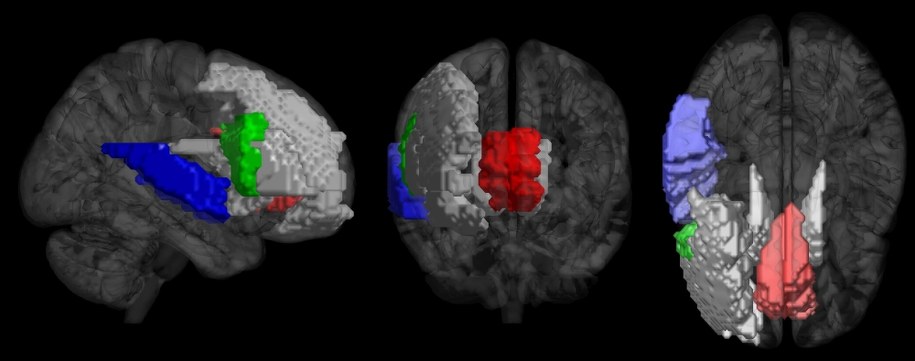

Do udziału w eksperymencie zaproszono 36 osób, 18 muzyków i 18 osób bez muzycznego przygotowania. Aktywność mózgu każdego z uczestników, podczas słuchania fragmentów muzyki różnych gatunków, badano z pomocą aparatury funkcjonalnego rezonansu magnetycznego. Okazało się, że edukacja muzyczna silnie wpływała na reakcje mózgu i można było na ich podstawie ocenić, kto taką edukację przeszedł. Najsilniej te różnice było widać w obszarach kory czołowej i skroniowej prawej półkuli mózgu.

Model był w stanie ocenić muzykalność danej osoby z 77 proc. dokładnością. Rejony mózgu, które najbardziej się do tego celu przydawały wiązano już wcześniej między innymi z uwagą i zaangażowaniem, a także z analizą muzyki i pojedynczych dźwięków. To rejony najbardziej zaangażowane w odbiór muzyki i najsilniej modyfikowane przez muzyczną edukację - podkreśla współautorka pracy: Iballa Burunat. Najlepszą wskazówką przy ocenie muzykalności była aktywność rejonów mózgu zajmujących się oceną rytmu i tonacji muzyki, to one prawdopodobnie podczas nauki muzyki stają się szczególnie wrażliwe.